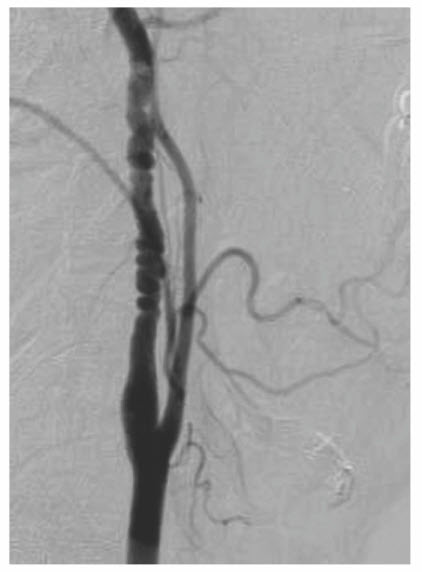

A carotid coil consists of an excessive elongation of the internal carotid artery producing tortuosity of the vessel (Fig. below). Embryologically, the carotid artery is derived from the third aortic arch and dorsal aortic root and is uncoiled as the heart and great vessels descend into the mediastinum. In children, carotid coils appear to be congenital in origin. In contrast, elongation and kinking of the carotid artery in adults are associated with the loss of elasticity and an abrupt angulation of the vessel. Kinking is more common in women than men. Cerebral ischemic symptoms caused by kinks of the carotid artery are similar to those from atherosclerotic carotid lesions but are more likely due to cerebral hypoperfusion than embolic episodes. Classically, sudden head rotation, flexion, or extension can accentuate the kink and provoke ischemic symptoms. Most carotid kinks and coils are found incidentally on carotid duplex scan. However, interpretation of the Doppler frequency shifts and spectral analysis in tortuous carotid arteries can be difficult because of the uncertain angle of insonation. Cerebral angiography, with multiple views taken in neck flexion, extension, and rotation, is useful in the determination of the clinical significance of kinks and coils.

Excessive elongation of the carotid artery can result in carotid kinking (arrow), which can compromise cerebral blood flow and lead to cerebral ischemia.